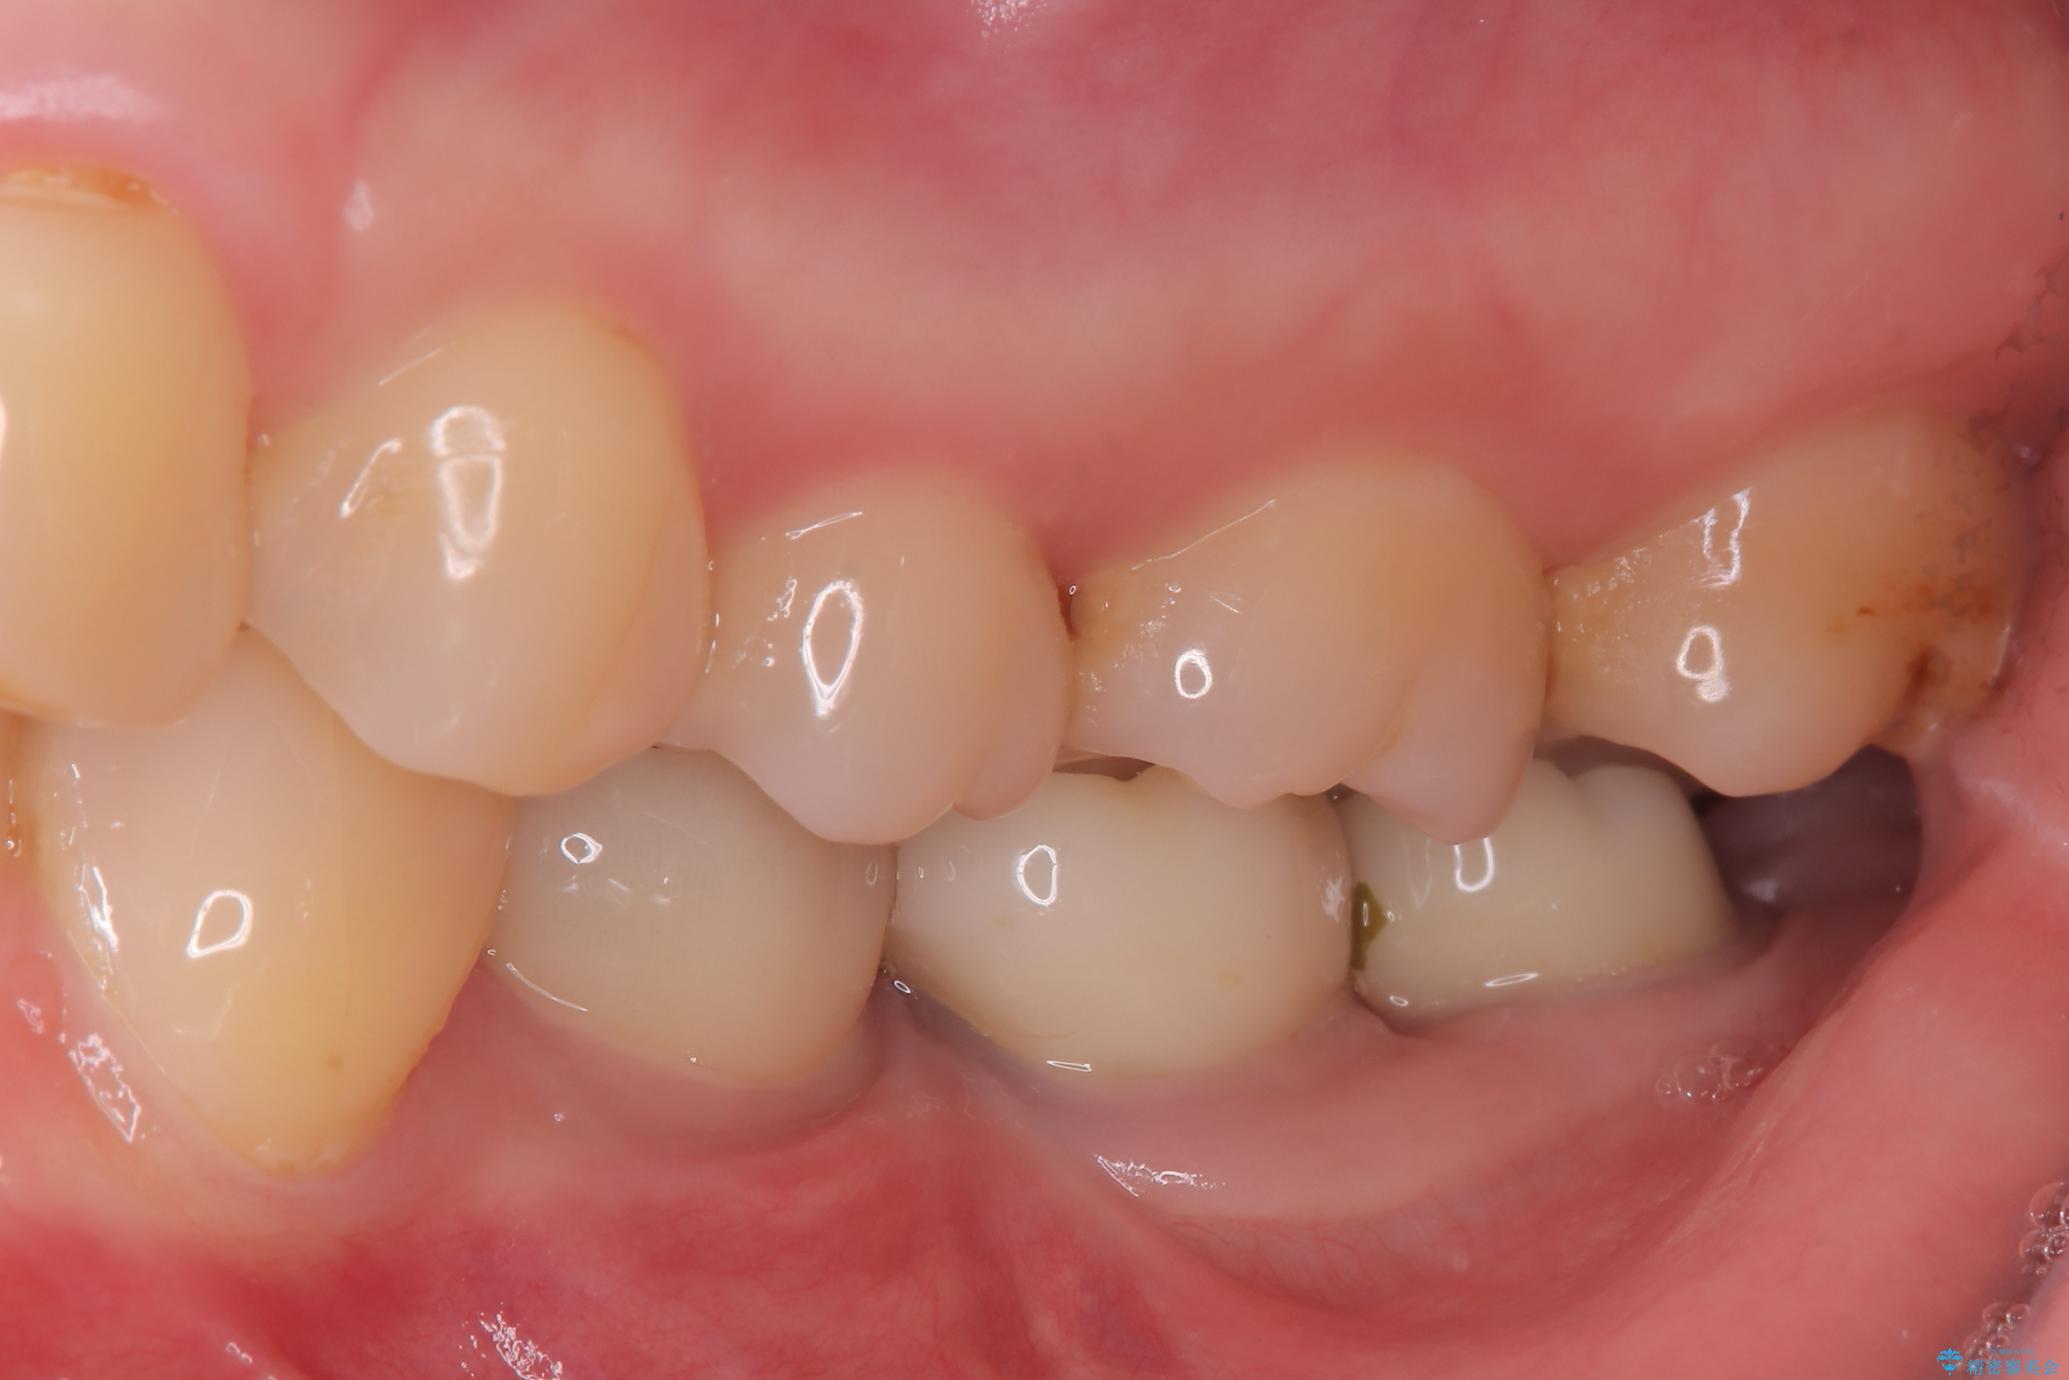

- 奥歯の虫歯治療を主訴にご来院されました。患者様から「できるだけ通院回数を少なく、早く治療を終わらせたい」というご要望があったため、短期間での完了を目指し、セラミックインレー(詰め物)とセラミッククラウン(被せ物)を併用する治療計画を立案しました。治療は精密機器を活用し、2回の来院で最終的なセラミック修復物を装着することを目指します。

今回の治療では、虫歯の大きさや深さに応じて、異なるセラミック修復法を適用しました。

比較的軽度な虫歯には、セラミックインレー(詰め物)で対応し、健全な歯質を最大限に残しました。

進行した虫歯や歯の強度が低下している歯には、セラミッククラウン(被せ物)を選択し、歯全体を保護することで破折を防ぎました。

短期間での治療を可能にしつつ、天然歯と見分けがつかない審美性と、長期的に安定する機能性を兼ね備えたセラミック修復を実現しました。